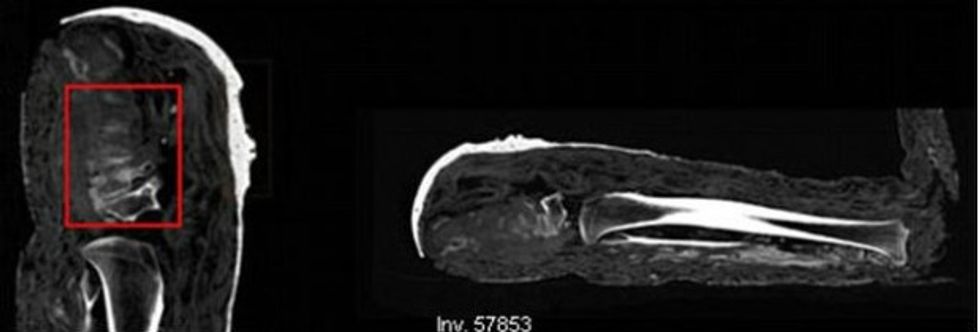

Using CT scans, X-rays and carbon dating to determine the age of each of the mummies, their examinations revealed that a second mummy was made up of a mixture of male and female bones along with a "modern nail." What's more, experts found hints of zinc and tin in the paints, elements they say would not have been used during the embalming of ancient mummies.